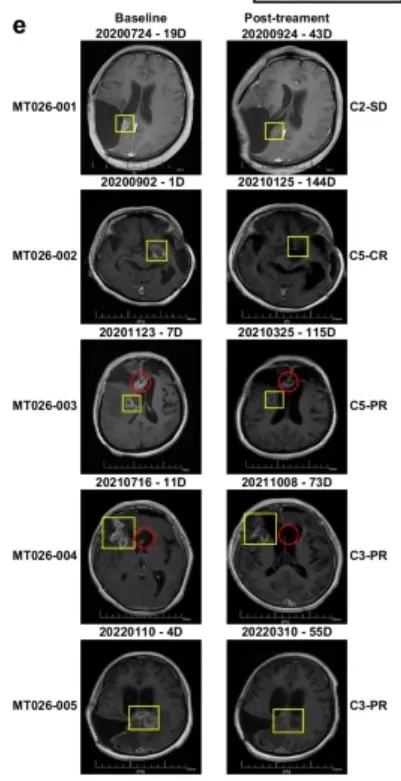

这项首次人体I期临床试验(试验编号:ChiCTR2000028801),共纳入5名复发高级别胶质瘤患者,这些患者均经过手术、放疗、替莫唑胺化疗等常规治疗失败,且病情危重,所有患者均为IDH野生型、MGMT启动子未甲基化(这两种都是预后极差的标志)。

就是这样一群被判定“预后极差”的患者,在接受MT026鞘内注射治疗后,交出了令人震撼的答卷:

客观缓解率80%:5名患者中,1名实现完全缓解(肿瘤完全消失),3名实现部分缓解(肿瘤明显缩小),1名病情稳定,没有1名患者出现病情进展,疾病控制率100%;

生存期大幅延长:从复发时间开始计算,患者的中位生存期达到13.1个月,12个月生存率80%,其中一名63岁的女性患者(MT026-002),复发后生存期更是达到了33.2个月,远超复发后6-8个月的中位生存期;

安全性极佳:所有治疗相关的不良事件均为1-2级,主要是发热、低氧血症、呕吐等轻微症状,均可自行缓解或经简单治疗后缓解,未出现任何3级及以上不良事件,也没有出现免疫效应细胞相关神经毒性综合征(ICANS)、感染等严重并发症。

要知道,这5名患者的病情,比以往同类临床试验中的患者更重,但MT026依然能取得这样的疗效,足以证明这款国研CAR-T的强大实力——它不仅打破了复发胶质瘤的治疗困局,更让我们看到了“治愈”的可能。